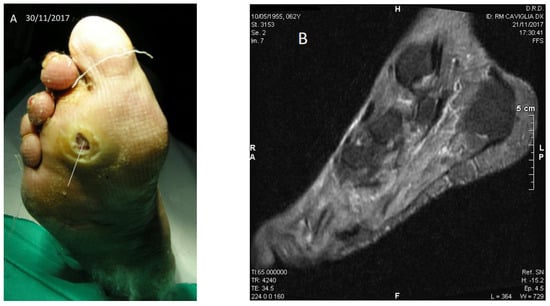

Figure 3.

Case No. 3. (A,C,D) Different moments of the wound healing, stable after six months; (B) NMR with the bone lesion at the third metatarsal ray.

Patient No. 3: P.C., 63-year-old female; diabetic since age 39; BMI = 36.3; former smoker; non alcoholic; from the age of 51 years Chronic Renal Failure; from the age of 60 she presented atrial fibrillation and flutter; carrying a plantar ulcer on the right foot for about three years (Figure 3A–D), penetrating the bone structure of the third distal metatarsal ray (Figure 3B). The patient was currently taking acetylsalicylic acid 100 mg/day, rapid insulin 3 mL 100 U/M (3 U at breakfast, 6 U at lunch, 8 U at dinner); slow insulin 3 mL 100 IU/M (14 U in the evening); also presented slight sensorial-motor polyneuropathy (class I); fasting blood glucose ~57 mg/dL (recurrent hypoglycemia); Urea 112 mg% (nr: 10–50); HbA1c DCCT = 7.9% (nr: 4–6); HbA1c IFCC = 63 mmol/mol (nr: 10–50).